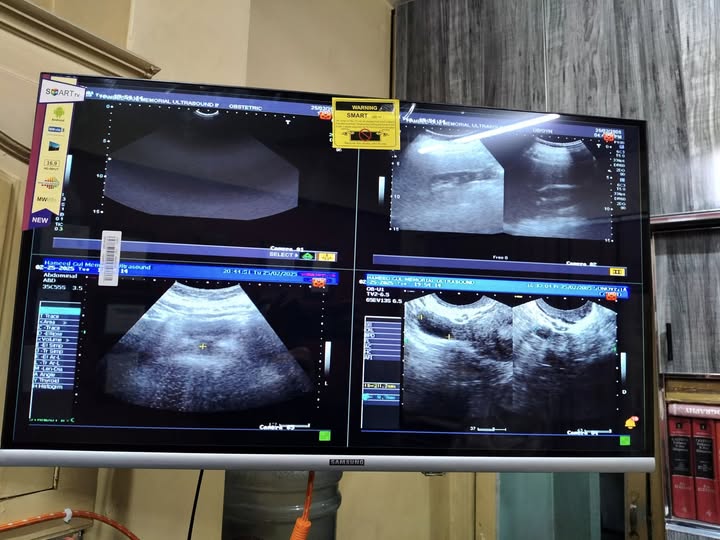

Learning Resources at Hameed Gul Memorial Ultrasound Institute and Clinics

At Hameed Gul Memorial Ultrasound Institute and Clinics, we take pride in offering a comprehensive and continually growing collection of ultrasound images and videos. Our archive spans the full spectrum—from the ultrasound appearance of normal anatomical structures to a wide range of pathological findings, including rare and complex cases seldom encountered in routine practice.

These valuable learning resources are meticulously curated and stored in our secure database. We regularly feature selected images and videos on our official website, providing an open platform for trainees, educators, and ultrasound professionals to engage in knowledge sharing, clinical discussion, and collaborative learning.

Our institutue provides high-quality ultrasound imagies for various diagnostic applications. these images serve as essential tools for accurate diagnostic and treatment planning.